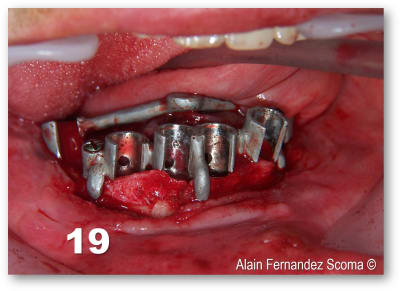

voici ce qui a été fait par un chirurgien maxillo en AG qui avait à son actif une vingtaine d'implants posés, la S.I.A.O (17), pose des guides à appuis osseux (18, 19), résultat fin de chirurgie (20).